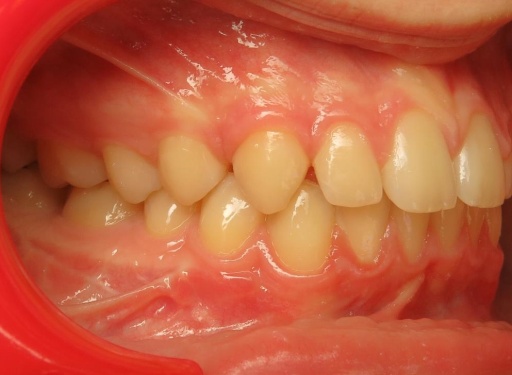

2 - Préparation orthodontique et résultat après chirurgie

Les photos supérieures montrent les arcades juste avant la chirurgie, avec un alignement complet et des axes dentaires physiologiques. La largeur de l’arcade maxillaire a été préparée pour permettre un emboîtement optimal après l’avancée mandibulaire. En bas, les photos post-opératoires montrent des arcades désormais coordonnées, avec une occlusion stable et harmonieuse, grâce à une préparation rigoureuse en amont de l’intervention chirurgicale.